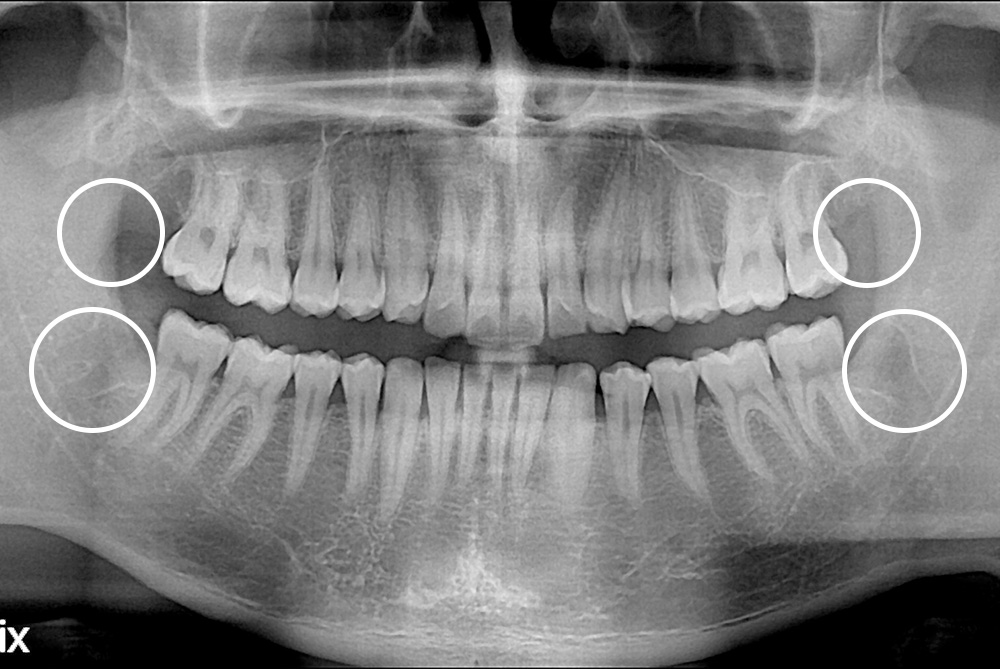

[사랑니] 매복 사랑니 발치

치료후 : 2019-06-06